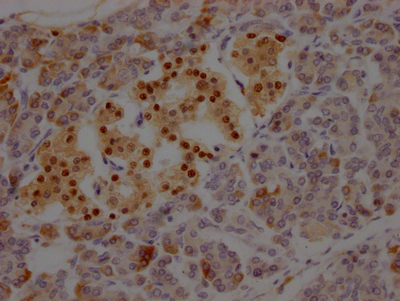

• IHC image of CSB-RA941933A0HU diluted at 1:100 and staining in paraffin-embedded human adrenal gland tissue performed on a Leica BondTM system. After dewaxing and hydration, antigen retrieval was mediated by high pressure in a citrate buffer (pH 6.0). Section was blocked with 10% normal goat serum 30min at RT. Then primary antibody (1% BSA) was incubated at 4℃ overnight. The primary is detected by a Goat anti-rabbit IgG polymer labeled by HRP and visualized using 0.05% DAB.

• IHC image of CSB-RA941933A0HU diluted at 1:100 and staining in paraffin-embedded human pancreatic tissue performed on a Leica BondTM system. After dewaxing and hydration, antigen retrieval was mediated by high pressure in a citrate buffer (pH 6.0). Section was blocked with 10% normal goat serum 30min at RT. Then primary antibody (1% BSA) was incubated at 4℃ overnight. The primary is detected by a Goat anti-rabbit IgG polymer labeled by HRP and visualized using 0.05% DAB.